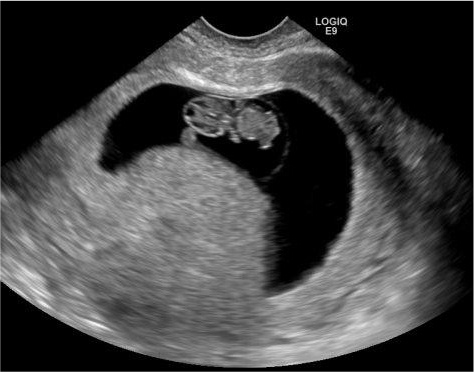

I was to follow up with my OB today so I gave them a call at 8:30am and she wanted me to have an ultrasound at 10. I headed over there and my friend Jennifer was able to meet me there since Jason was at work. I was thankful she offered because I seem to always be so tough but I thought if something is wrong it might be good to have someone there. Everything looked great. The tech I think could have looked at baby all day if she don't have other appointments. We were there almost an hour, she was very thorough and knew a bit about our journey with infertility and wanted to make sure she checked everything. So feet up this weekend which is fine I have a bit of studying to do.

Profile picture of her with mouth open. We were watching her move her tongue and open and close her mouth. Amazing what they can see.